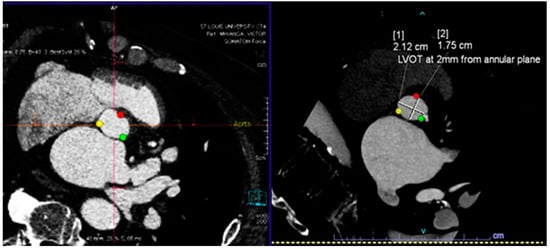

| Santaló-Corcoy [20] | 200 CTs (35 for training, and 17 for testing) | Manual CT measurement by an expert cardiologist using 3Mensio. | Correlation between manual and automated measurements | DL algorithms (MeshDeformNet) for landmark detection followed by segmentation | mean absolute relative error was within 5% for most measurements, except for coronary height (11.6% and 16.5%). |

| Theriault-Lauzier [21] | 94 CTs of severe AS (K-fold cross-validation with K=) | Manually segmented AV annulus | Correlation between manual and automated measurements | recursive multiresolution CNN for localization of the AV annulus centroid | average out-of-plane localization error of 0.9 ± 0.8 mm for the evaluation dataset. The proposed algorithm is on par with automated methods for localization and approaches in providing an expert-level accuracy. |

- Santaló-Corcoy, M.; Corbin, D.; Tastet, O.; Lesage, F.; Modine, T.; Asgar, A.; Ben Ali, W. TAVI-PREP: A Deep Learning-Based Tool for Automated Measurements Extraction in TAVI Planning. Diagnostics 2023, 13, 3181. [Google Scholar] [CrossRef]